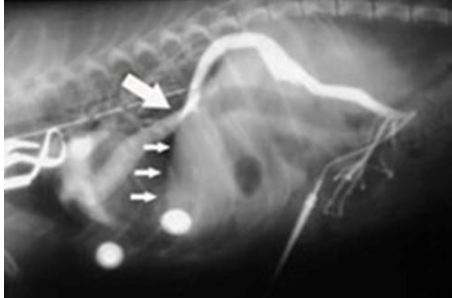

what does the radiograph show?

portosystemic shunt and loss of portal flow to liver